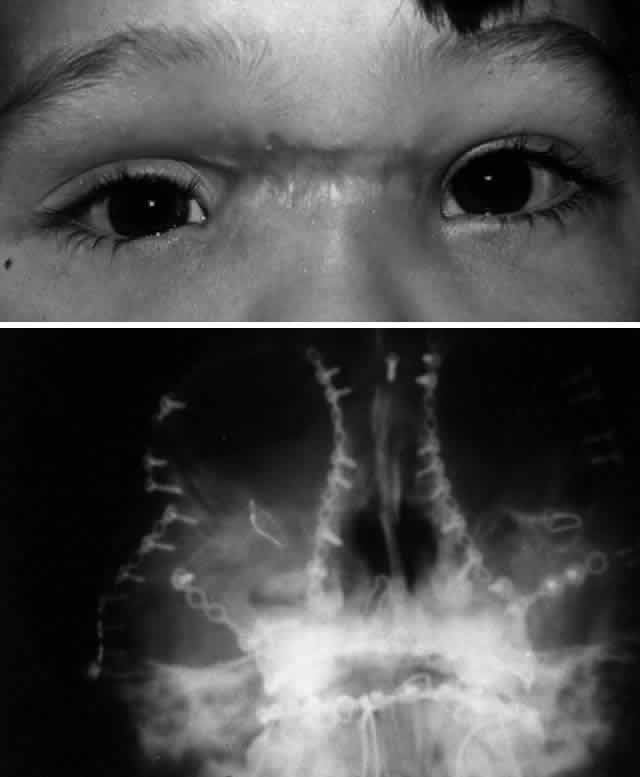

The position of the globe is also assessed (Fig. 3). As detailed previously, outward expansion of the orbital walls (blow-out fractures) can produce enophthalmos. Inward expansion of the orbital walls (blow-in fractures) can reduce orbital volume, potentially producing exophthalmos. In the early period after blunt orbital trauma, orbital edema and hemorrhage can transiently increase the orbital soft tissue volume, producing exophthalmos or “masking” the underlying potential for enophthalmos. As orbital edema subsides, the true globe position becomes evident. Over a more extended period of time (several months), soft tissue changes (cicatrization and, less commonly, fat atrophy) may contribute to the production of late enophthalmos. Globe position can be grossly assessed by direct visual inspection. Viewing the axial projection of the globes from above (“bird's-eye view”) or from below (“worm's-eye view”) facilitates a gross determination of axial globe position.

After the history and physical examination, consideration is given to further assessment of the orbital injury with radiologic imaging. The indications for radiologic imaging area are based on the physician's assessment of the injury and include gross orbital and facial deformity, limitation of ocular motility, and associated neurologic injuries. CT is the imaging modality of choice in the assessment of orbital/craniofacial fractures because it provides excellent detail of the bony injury as well as the orbital soft tissues in most cases (Fig. 4). Ideally, both axial and direct coronal views are preferred. Coronal views are necessary for adequate imaging of the orbital floor and orbital roof. With direct views, 3-mm views (cuts) are usually adequate. In cases in which the patients cannot be positioned for direct coronal imaging, coronal reconstructions can be performed, provided that finer (1.5-mm) axial cuts are used. Reconstructed coronal images lack the resolution of direct coronal images, but they are usually adequate when direct coronal imaging cannot be obtained. Spiral CT, which allows rapid imaging and multiplanar formatting, will likely become useful in the assessment of orbital trauma as this newer technology becomes increasingly available.

Fig. 4. Same patient as depicted in Figure 3. A. Water's view. Facial x-ray shows ill-defined left inferior orbital floor fracture with soft tissue mass in superior left maxillary sinus. B. Coronal CT scan shows superior resolution of left orbital floor defect, with prolapse of orbital soft tissues into the maxillary sinus. Note distortion of left inferior rectus muscle. Floor defects greater than 50% are more likely to produce enophthalmos.

Before CT scanning was readily available, facial x-ray series were used in the radiologic assessment of orbital fractures. Typical views included Caldwell's (anteroposterior) view, Waters' view, lateral view, and submental vertex view (particularly good for viewing the zygomatic arches). Waters' view, which is obtained with the chin slightly elevated, is considered the most useful x-ray view for imaging the orbital floor, inferior rim, and maxillary sinus. Because CT scans are superior to x-rays in terms of sensitivity and reliability, in most situations today plain orbital/facial x-rays are obtained only when a CT scan is unavailable or when only very minimal injury is suspected. Magnetic resonance imaging (MRI), although able to image orbital soft tissue exquisitely well with a small surface coil, is generally of limited usefulness in the initial assessment of orbital/craniofacial injuries because of its limited ability to image bone. It is contraindicated in cases of suspected retained ferromagnetic foreign bodies. MRI may have a secondary role in the management of orbital trauma in cases where CT scanning suggests the presence of soft tissue injury, such as intramuscular hemorrhage or sub-dural optic nerve sheath hemorrhage. In such cases, the better soft tissue resolution potentially available with MRI may allow more specific diagnostic interpretation.2